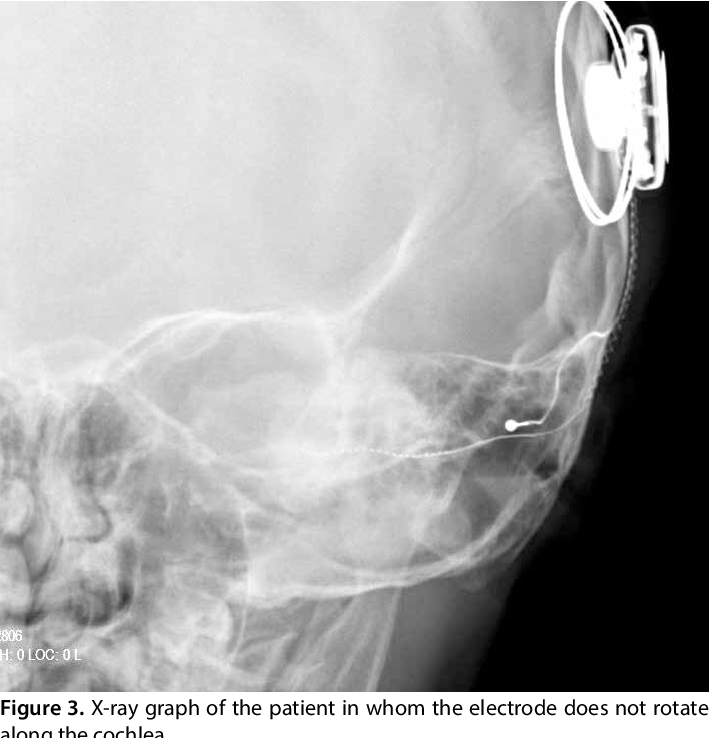

The inner part is placed under the skin behind the ear during outpatient surgery. A thin wire and small electrodes lead to the cochlea, which is part of the inner ear. The wire sends signals to the cochlear nerve, which sends sound information to the brain to produce an auditory sensation.